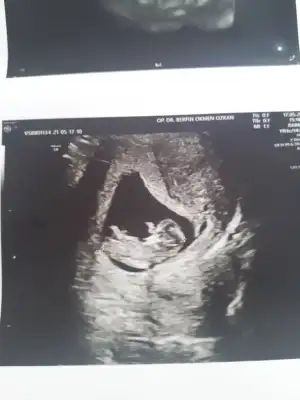

Merhaba nolur benim için de yorumda bulunun mümkün ise🙏🏻 Ikra meyra Ikra meyra şimdiden çok tşk ederim🌻

Ikra meyra Ikra meyra merhabaaa Canım :) Arkadaşımın bebisinin fotosunu atiyorum.Sana zahmet tahminde bulunabilirsen çoooook sevinirim :) Şu an 12+2 :)